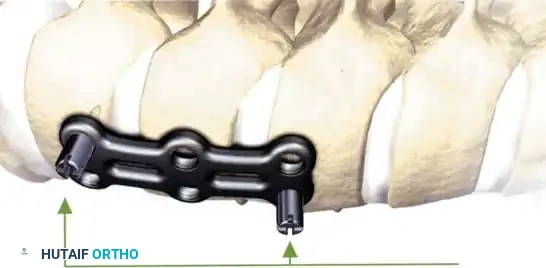

Anterior Cervical Discectomy and Fusion (ACDF)

Indications: Anterior column compromise, extruded traumatic disc herniations, or as the first stage in a 360-degree fusion for severe distractive flexion injuries.

Surgical Steps:

1. Exposure: Retract the longus colli muscles laterally to expose the anterior vertebral bodies and the damaged disc space.

2. Discectomy: Perform a complete discectomy using curettes and pituitary rongeurs. In trauma, the PLL is often torn; carefully remove any extruded disc fragments compressing the cord.

3. Endplate Preparation: Decorticate the cartilaginous endplates using a high-speed burr to expose bleeding subchondral bone, ensuring a robust fusion bed.

4. Grafting: Insert a structural allograft or PEEK cage packed with autograft/demineralized bone matrix (DBM) into the disc space.

5. Plating: Apply a rigid anterior cervical plate. Ensure screws are placed parallel to the endplates and do not breach the adjacent disc spaces.

Fig 6. Anterior cervical plating construct providing rigid stabilization of the anterior column.